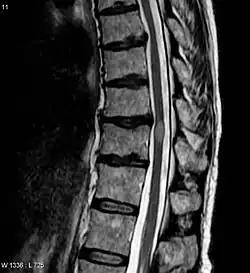

| Acute myelitis | intramedullary lesion > 3 contiguous segments, or spinal atrophy ≥ 3 contiguous segments |